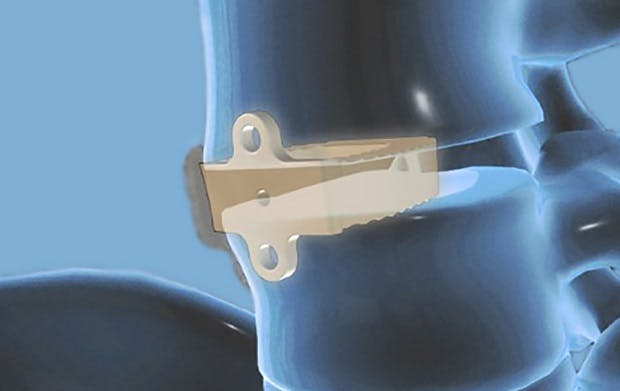

Omnia Medical's Boxcar is the first cervical VBR system to be made from PEEK-OPTIMA™ HA Enhanced, from Invibio.  © JALEX Medical

press release

Omnia Medical Receives First Ever 510(k) Clearance for PEEK-OPTIMA™ HA Enhanced Cervical VBR